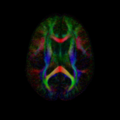

File:Goodlett-nccfaaxial039.png

Goodlett-nccfaaxial039.png (256 × 256 pixels, file size: 43 KB, MIME type: image/png)